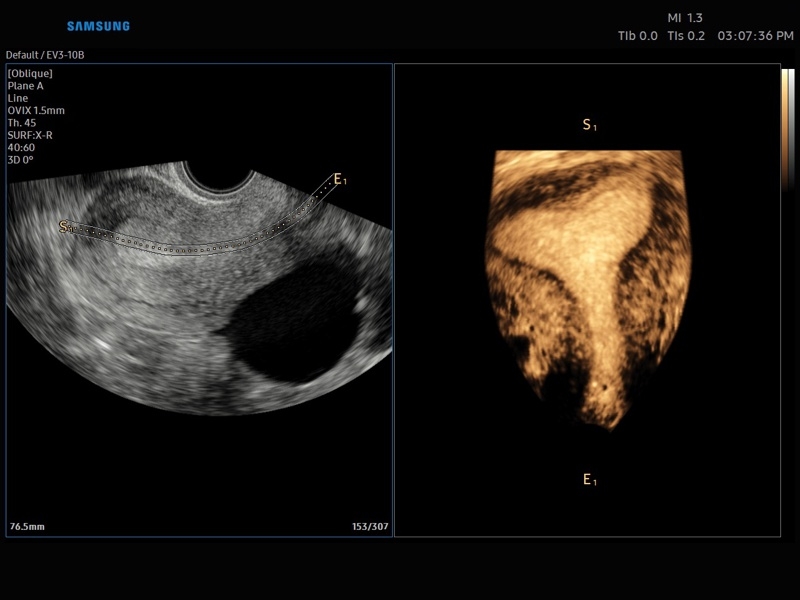

• OVIX(Oblique View eXtended) - получение фрагмента трехмерного изображения (в виде нескольких полупрозрачных сканов, последовательно наложенных один на другой) в направлении произвольного косого среза трехмерного объекта исследования.